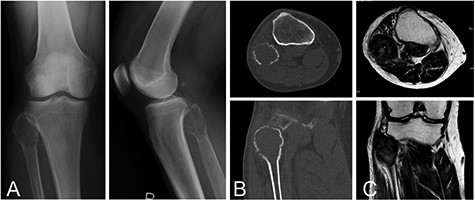

A 55-year-old male with GCTB in the proximal fibula. Plain radiographs (A) and computed tomography (B) show an osteolytic and expansive lesion. On magnetic resonance imaging, the lesion has a heterogeneous low-to-intermediate signal intensity on the T2-weighted image (C)

The patient was a 55-year-old male. He had noticed a pain in the left proximal lower leg 3 months earlier, after jumping from a 50 cm height. The patient was referred to our institute on the diagnosis of bone tumor. The pain had disappeared 1 month after the injury. Physical examination revealed no swelling and slight tenderness at the fibular head. Laboratory studies showed no remarkable findings. A plain radiograph and computed tomography showed an expansive and osteolytic lesion, involving the proximal fibular head (Figs. 1A and B). Magnetic resonance imaging of the lesion showed homogenous intermediate signal intensity on a T1-weighted image and heterogeneous low-to-intermediate signal intensity on a T2-weighted image (Fig. 1C). Based on the results of a needle biopsy, the diagnosis of GCTB was confirmed.